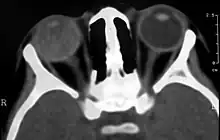

Computed Tomography image of a patient with Coats' disease, showing total exudative retinal detachment in the right eye

Imaging studies such as ultrasonography (US), Computerized Tomography (CT) and Magnetic Resonance Imaging (MRI) can aid diagnosis. On ultrasound, Coats' disease appears as a hyperechoic mass in the posterior vitreous without posterior acoustic shadowing; vitreous and subretinal hemorrhage may often be observed.[7][8]

On CT, the globe appears hyperdense compared to normal vitreous due to the proteinaceous exudate, which may obliterate the vitreous space in advanced disease. The anterior margin of the subretinal exudate enhances with contrast. Since the retina is fixed posteriorly at the optic disc, this enhancement has a V-shaped configuration.[2]